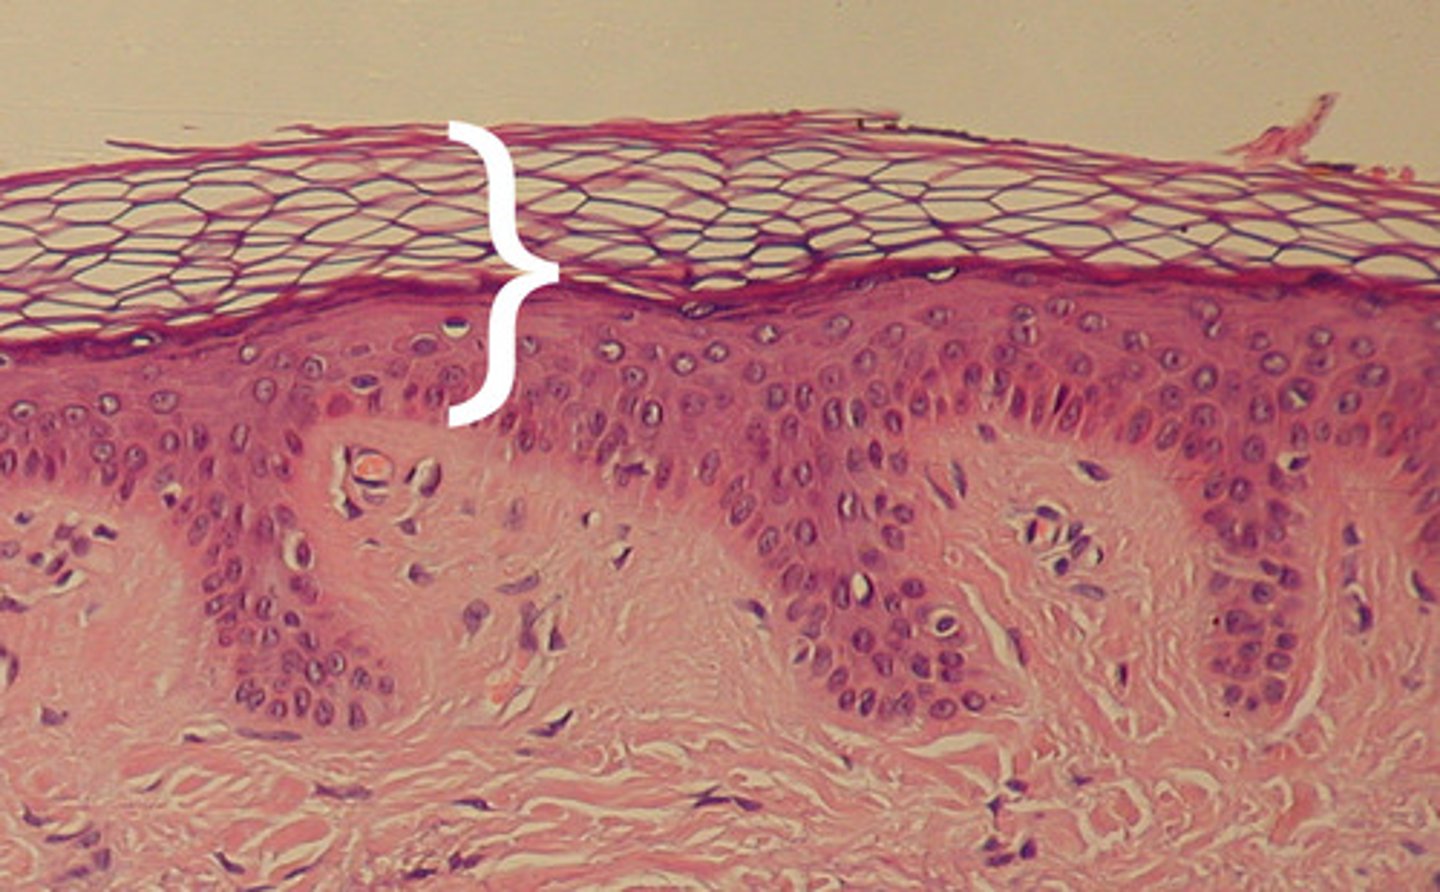

stratum corneum

outermost layer of epidermis

stratum lucidum

a layer of the epidermis found only in the thick skin of the fingers, palms, and soles

stratum spinosum

a layer of the epidermis that provides strength and flexibility to the skin

stratum basale

deepest layer of epidermis

Epidermis

Outer layer of skin

Epidermis is made up of

keratinized stratified squamous epithelium

thick skin

Covers the palms of the hands and soles of the feet

Has five layers of keratinocytes